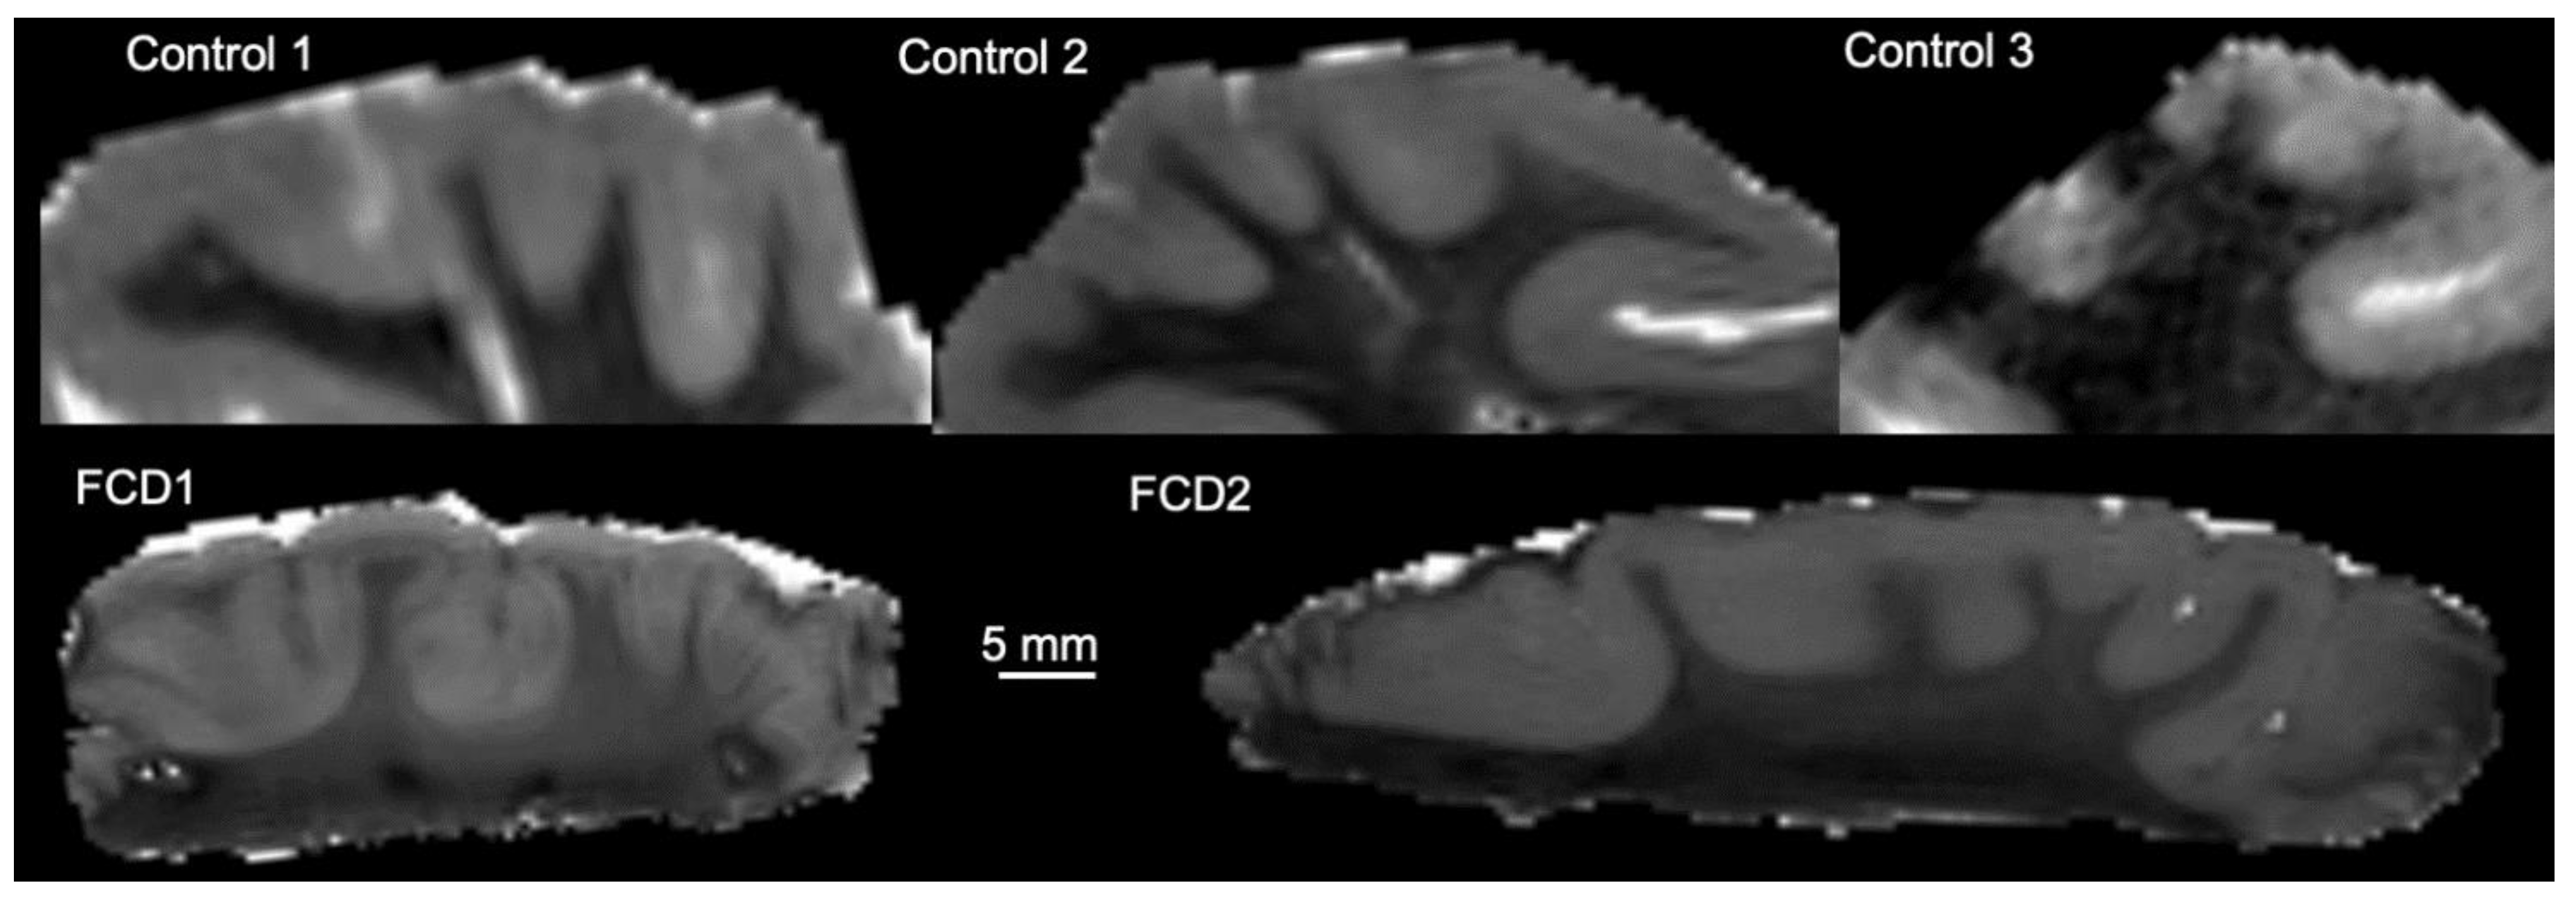

3.1. Magnetic Resonance (MR)-Histology of the Excised Human Cortex

3.2. Mesoscale Diffusion Characteristics of Cortical Dysplasia

3.3. Histological Underpinnings of Grey Matter Abnormalities